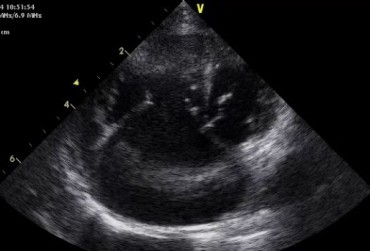

Dysplazja zastawki trójdzielnej i zespół Wolffa–Parkinsona–White’a u kota – opis przypadku

Zwężenie zastawki trójdzielnej jest jedną z form dysplazji pojawiającą się w różnym stopniu nasilenia (najczęściej łącznie z niedomykalnością zastawki) zarówno u psów, jak i u kotów. Cechami charakterystycznymi definiującymi zwężenie zastawki trójdzielnej są: obecność rozkurczowego wybrzuszenia (doming) płatków zastawki, zmniejszona ruchomość płatków, zmniejszona średnica ujścia zastawki. Mimo że zmiany morfologiczne aparatu trójdzielnego są typowe w przebiegu TVD i są znakiem rozpoznawczym tej choroby, nie są one zawsze bardzo silnie wyrażone i nie zawsze można mieć bezsprzeczną pewność diagnostyczną, bazując na badaniu echokardiograficznym [10]. Przypadki takie zdarzają się przede wszystkim u pacjentów, u których nie postawiono diagnozy we wczesnym etapie życia, a którzy pojawiają się na badaniu dopiero w starszym wieku z zaawansowanymi zmianami i niejednokrotnie z klinicznymi objawami prawostronnej niewydolności mięśnia sercowego i towarzyszącymi zaburzeniami w rytmie. W takich przypadkach obraz choroby może przypominać arytmogenną kardiomiopatię prawokomorową (arrhythmogenic right ventricular cardiomyopathy – ARVC) [1, 8]. Preekscytacja jest często obserwowana u ludzi z anomalią Ebsteina. U zwierzat, podobnie jak u ludzi, obecność dodatkowej drogi przewodzenia może nigdy nie prowadzić do rozwoju tachykardii nadkomorowej lub arytmia ta pojawiać się może dopiero w późniejszym okresie życia. Opisany przypadek jest przykładem pacjenta z dysplazją zastawki trójdzielnej i prawostronną niewydolnością serca będącą najprawdopodobniej konsekwencją tachykardii nadkomorowej.